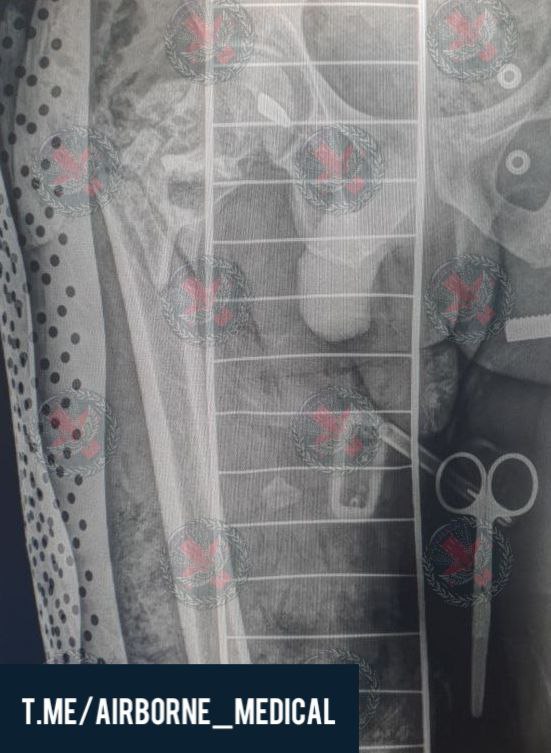

Пример неклассического использования КСВП, а именно в режиме "предплечье-кисть"

Боец попал под миномётный обстрел. В результате чего получил ранение с переломом лучевой кости, повреждением одноимённой артерии и массивным дефектом мягких тканей

После ревизии раны и оценки рентгенограмм принято решение о необходимости фиксации и кисти и лучевой кости.

Оперативное пособием прошло без негативных нюансов